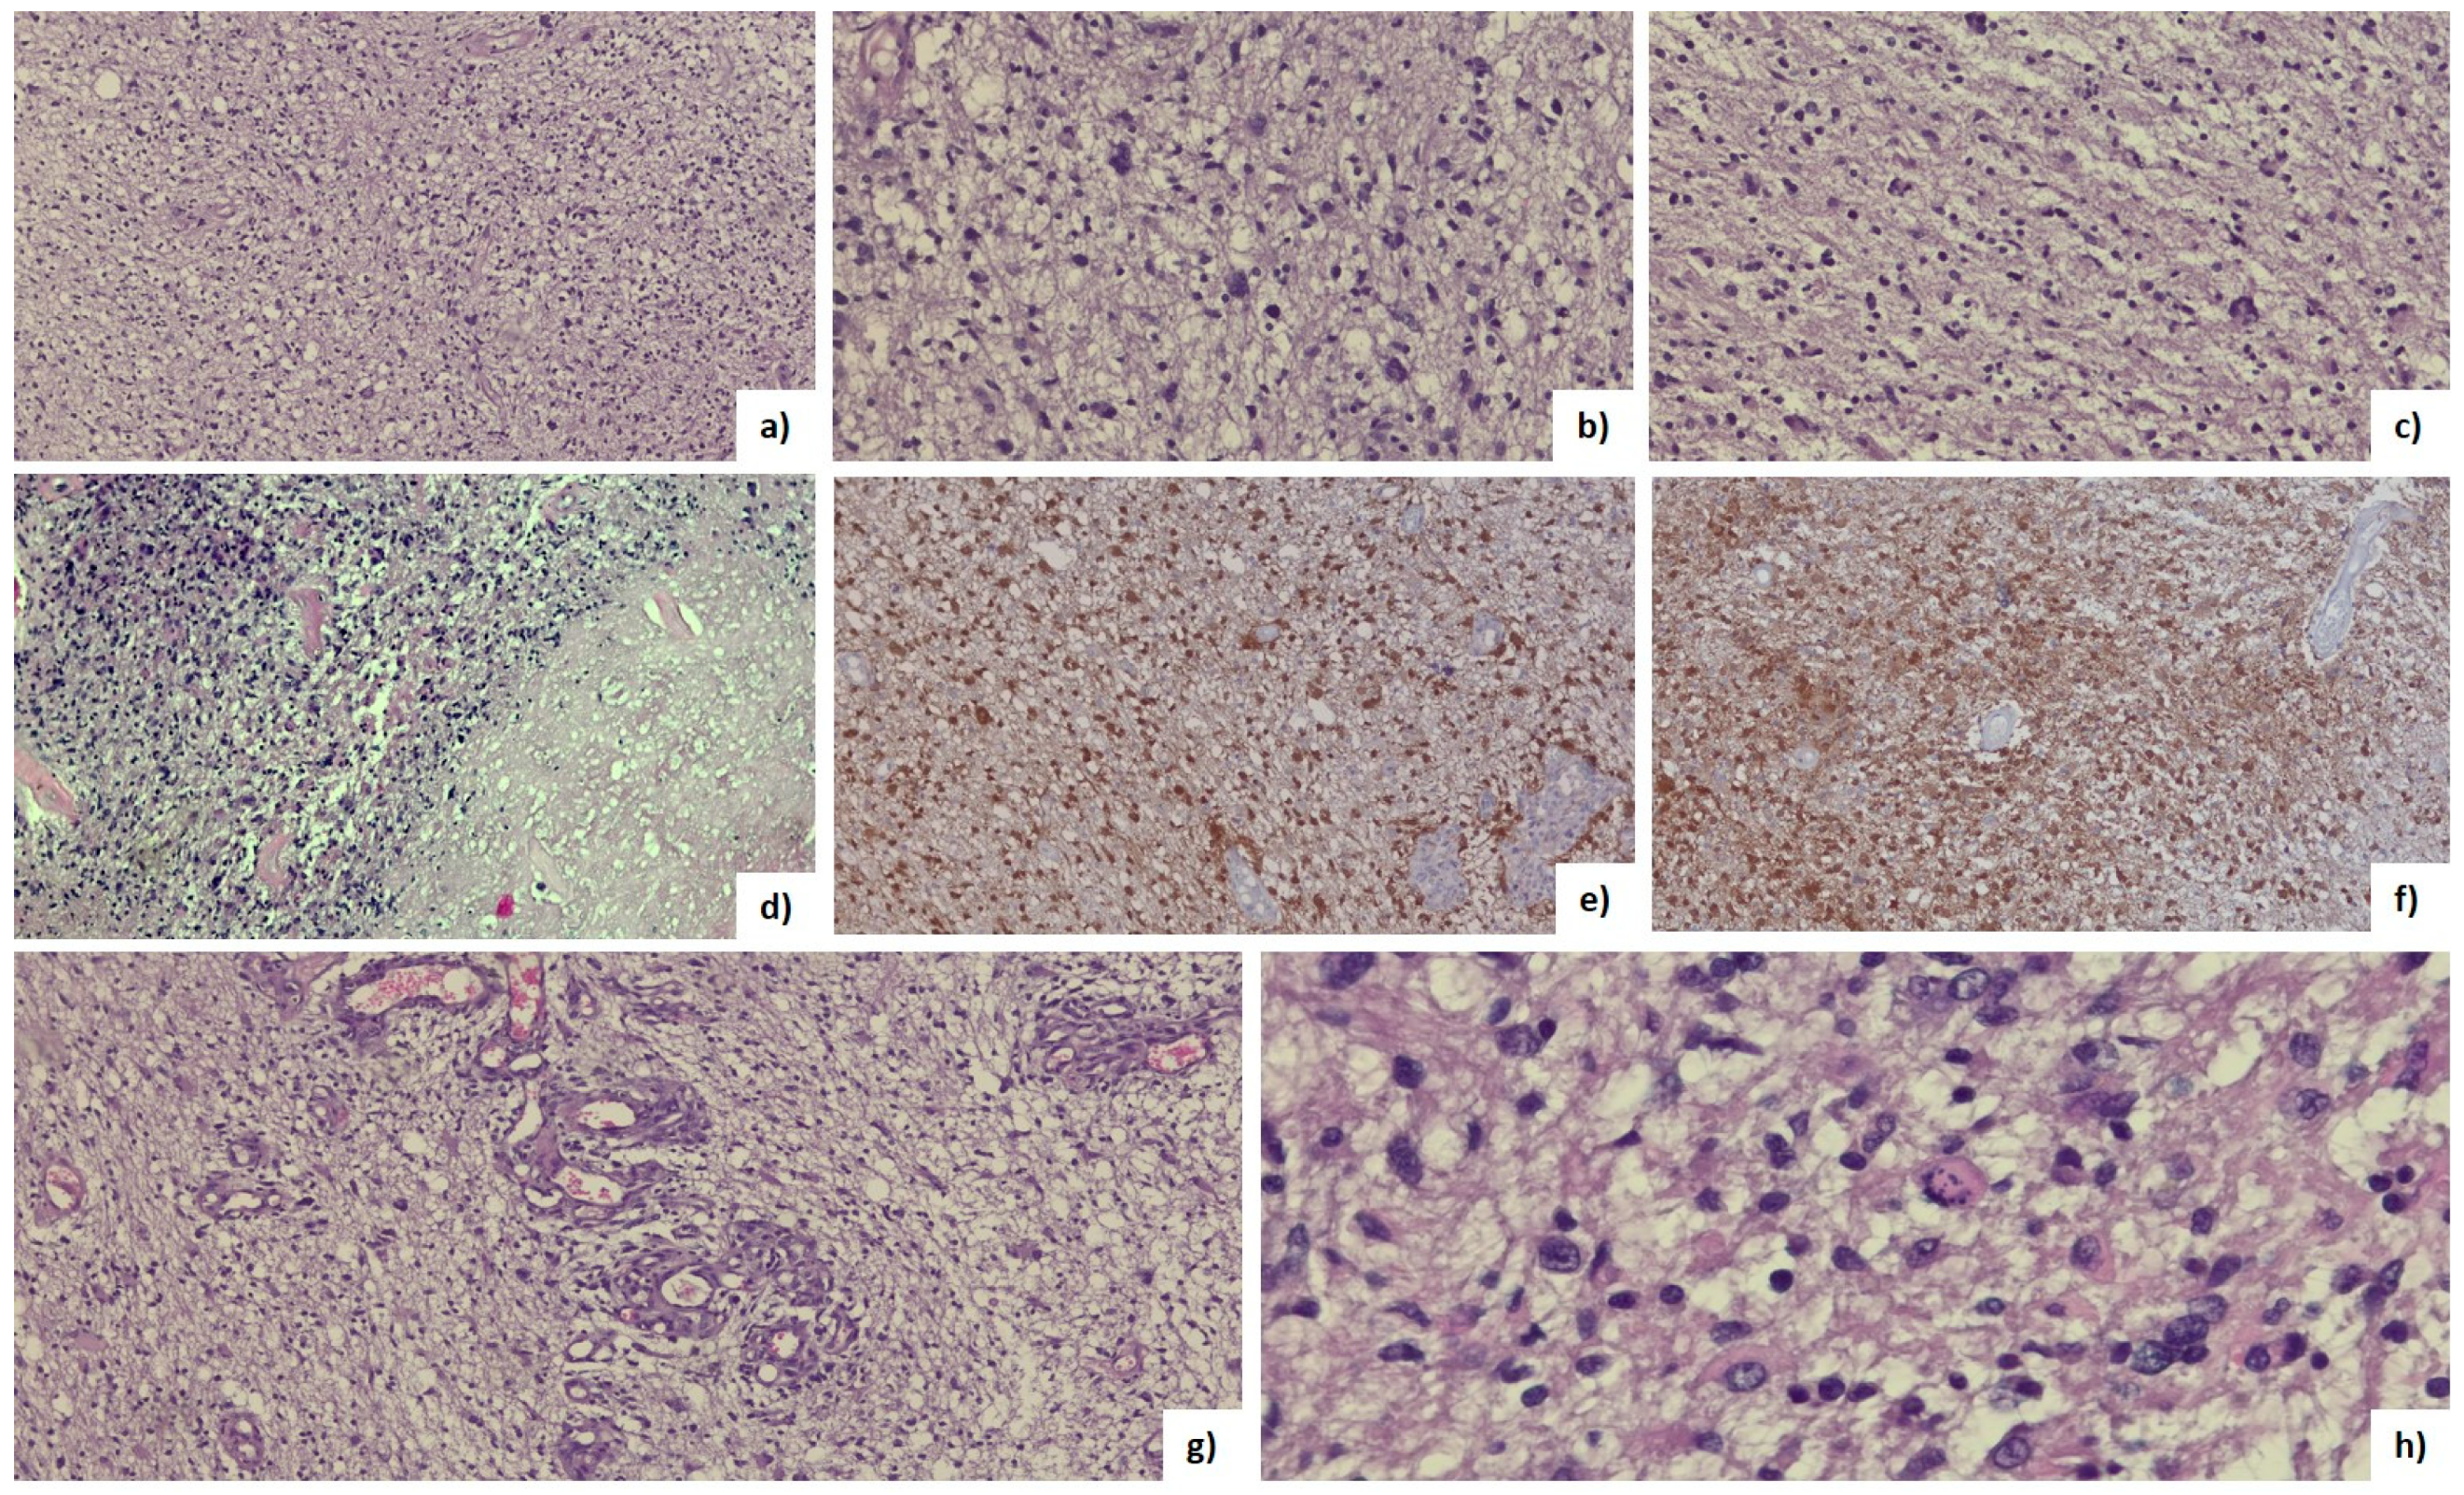

2.8. Histopathological Analysis

3.4. Histopathological Features